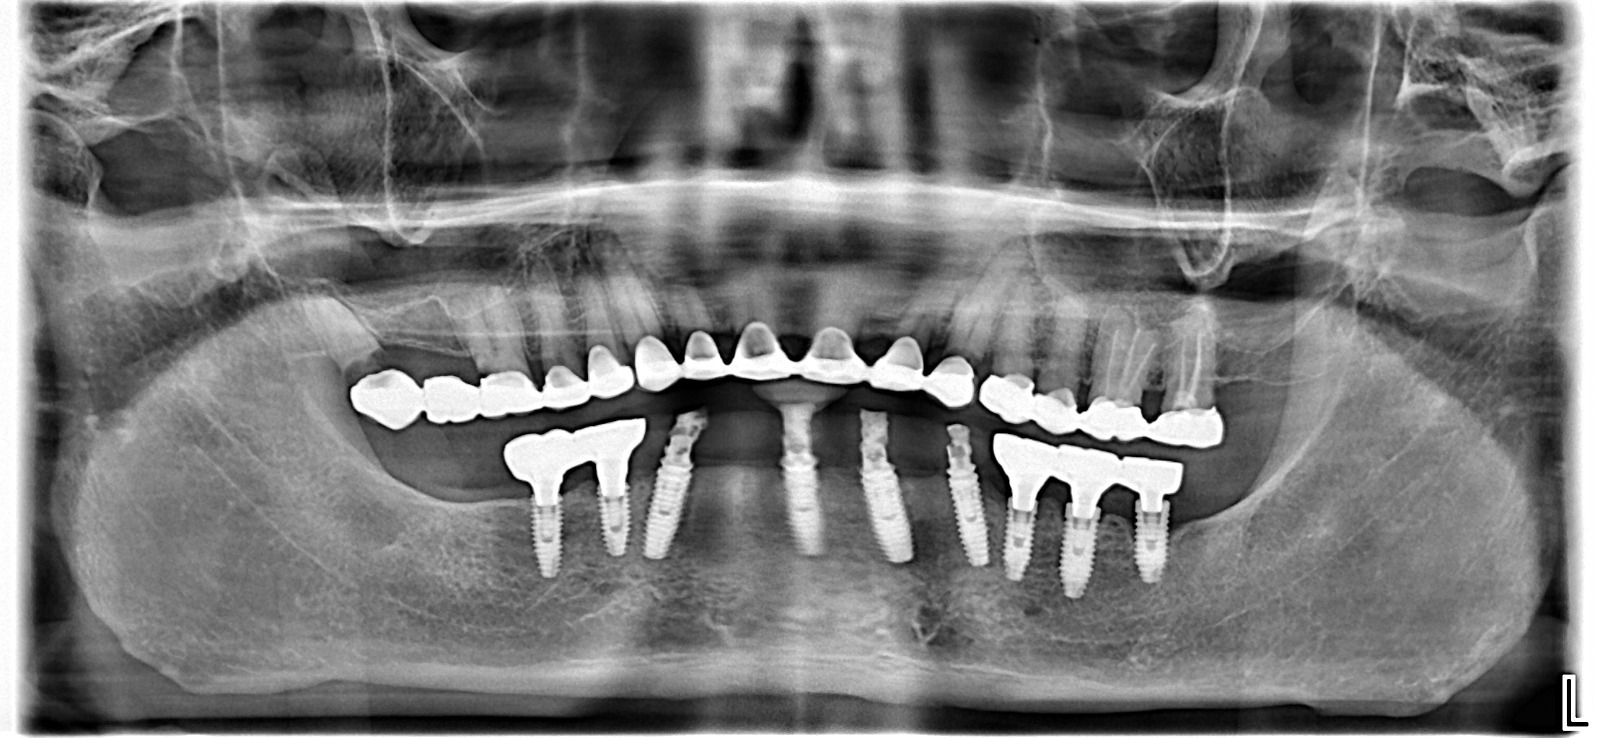

✅ Guided Implant Surgery

Using digital scans and planning software, implants are placed with extreme precision.

Benefits include:

• Accurate implant position

• Minimal surgical trauma

• Faster healing

• Safer outcomes

• Predictable long-term success

This is especially valuable for complex implant cases.